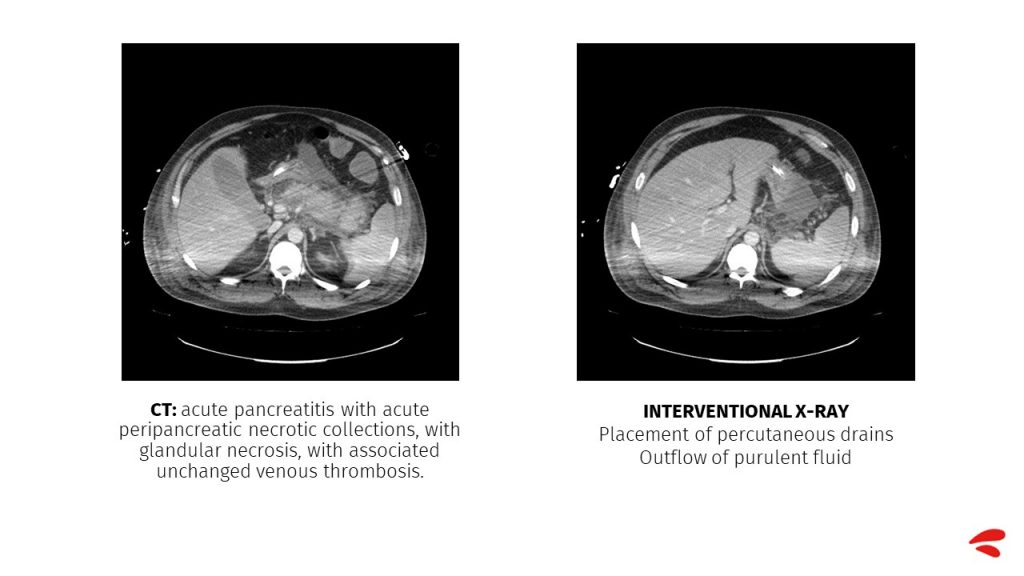

A repeat abdominal CT scan showed acute pancreatitis with acute peripancreatic necrotic collections, with glandular necrosis, and a previous venous thrombosis unchanged from the first test.

This CT scan shows pancreatitis with pancreatic and peripancreatic necrosis but no new complications. What is seen is the splenic infarction, which was already visualised after the splenic vein thrombosis.